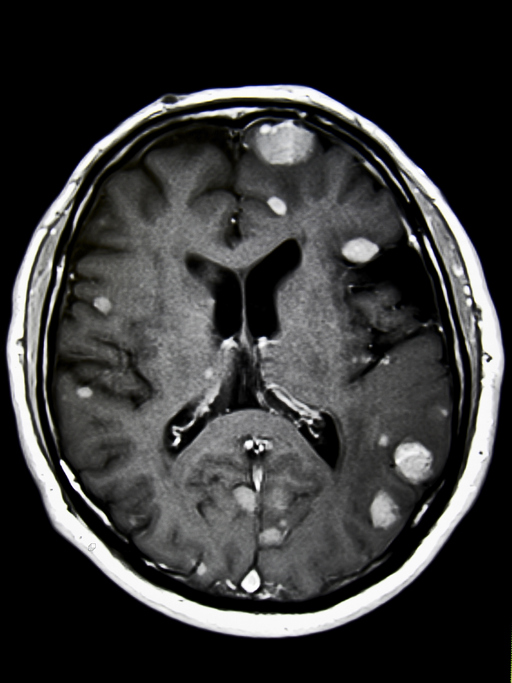

May 10, 2022 A new clinical guideline from the American Society for Radiation Oncology (ASTRO) provides guidance on the use of radiation therapy to treat patients with brain metastases. Evidence-bas… [+7507 chars]